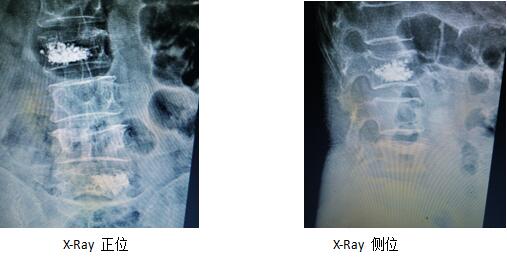

術(shù)后復(fù)查片(骨水泥彌散均勻,無外漏)